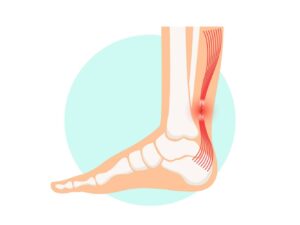

Die Orthopädie ist ein medizinisches Fachgebiet, das sich mit der Prävention, Diagnose und Behandlung von Erkrankungen und Verletzungen des Bewegungsapparates beschäftigt. Knochen, Gelenke, Muskeln, Sehnen und Bänder müssen gemeinsam funktionieren, um uns Beweglichkeit und Stabilität zu ermöglichen.

Auf unserer Seite finden Sie umfangreiche Informationen zu orthopädischen Beschwerden und Erkrankungen. Von der Arthrose über Bandscheibenvorfälle bis hin zu Kreuzbandriss und weiteren Sportverletzungen: wir geben Ihnen einen Überblick über die häufigsten orthopädischen Krankheitsbilder, wie sie behandelt werden können und inwieweit ein Bildgebungsverfahren, wie eine (z.B. MRT Knie, Rücken MRT) bei der Diagnose bei der Diagnose unterstützend wirken können.

Viele Betroffene suchen online nach den Ursachen oder Behandlungsmöglichkeiten von Rückenschmerzen, Bänderriss am Fuß oder Bandscheibenvorfall. Einige der orthopädische Beschwerden oder Verletzungen benötigen zu Behandlung eine Bildgebung und Therapie. Alle relevanten Informationen lesen Sie in den jeweiligen Beiträgen.